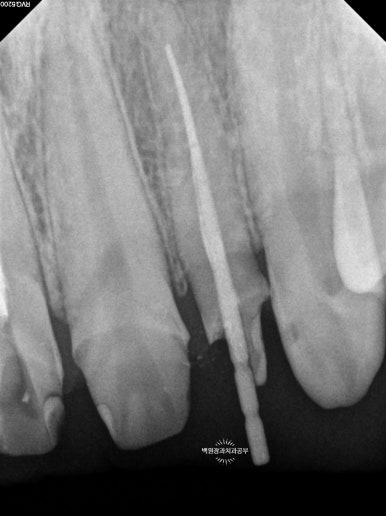

해당 치아들을 신경치료 하였습니다.

그리고 기둥을 세웠습니다.

신경치료가 완료되면 해당 치아속의 재료는 방사선 사진 상 하얗게 표시되게 됩니다.

신경치료 완료 후 남은 치아가 너무 적은 경우에는 치아 내부에 기둥 (=포스트)를 설치하게 됩니다.

눈에 보이는 부분의 치아가 너무 적으니 내부에서라도 힘을 얻으려는 노력이지요.